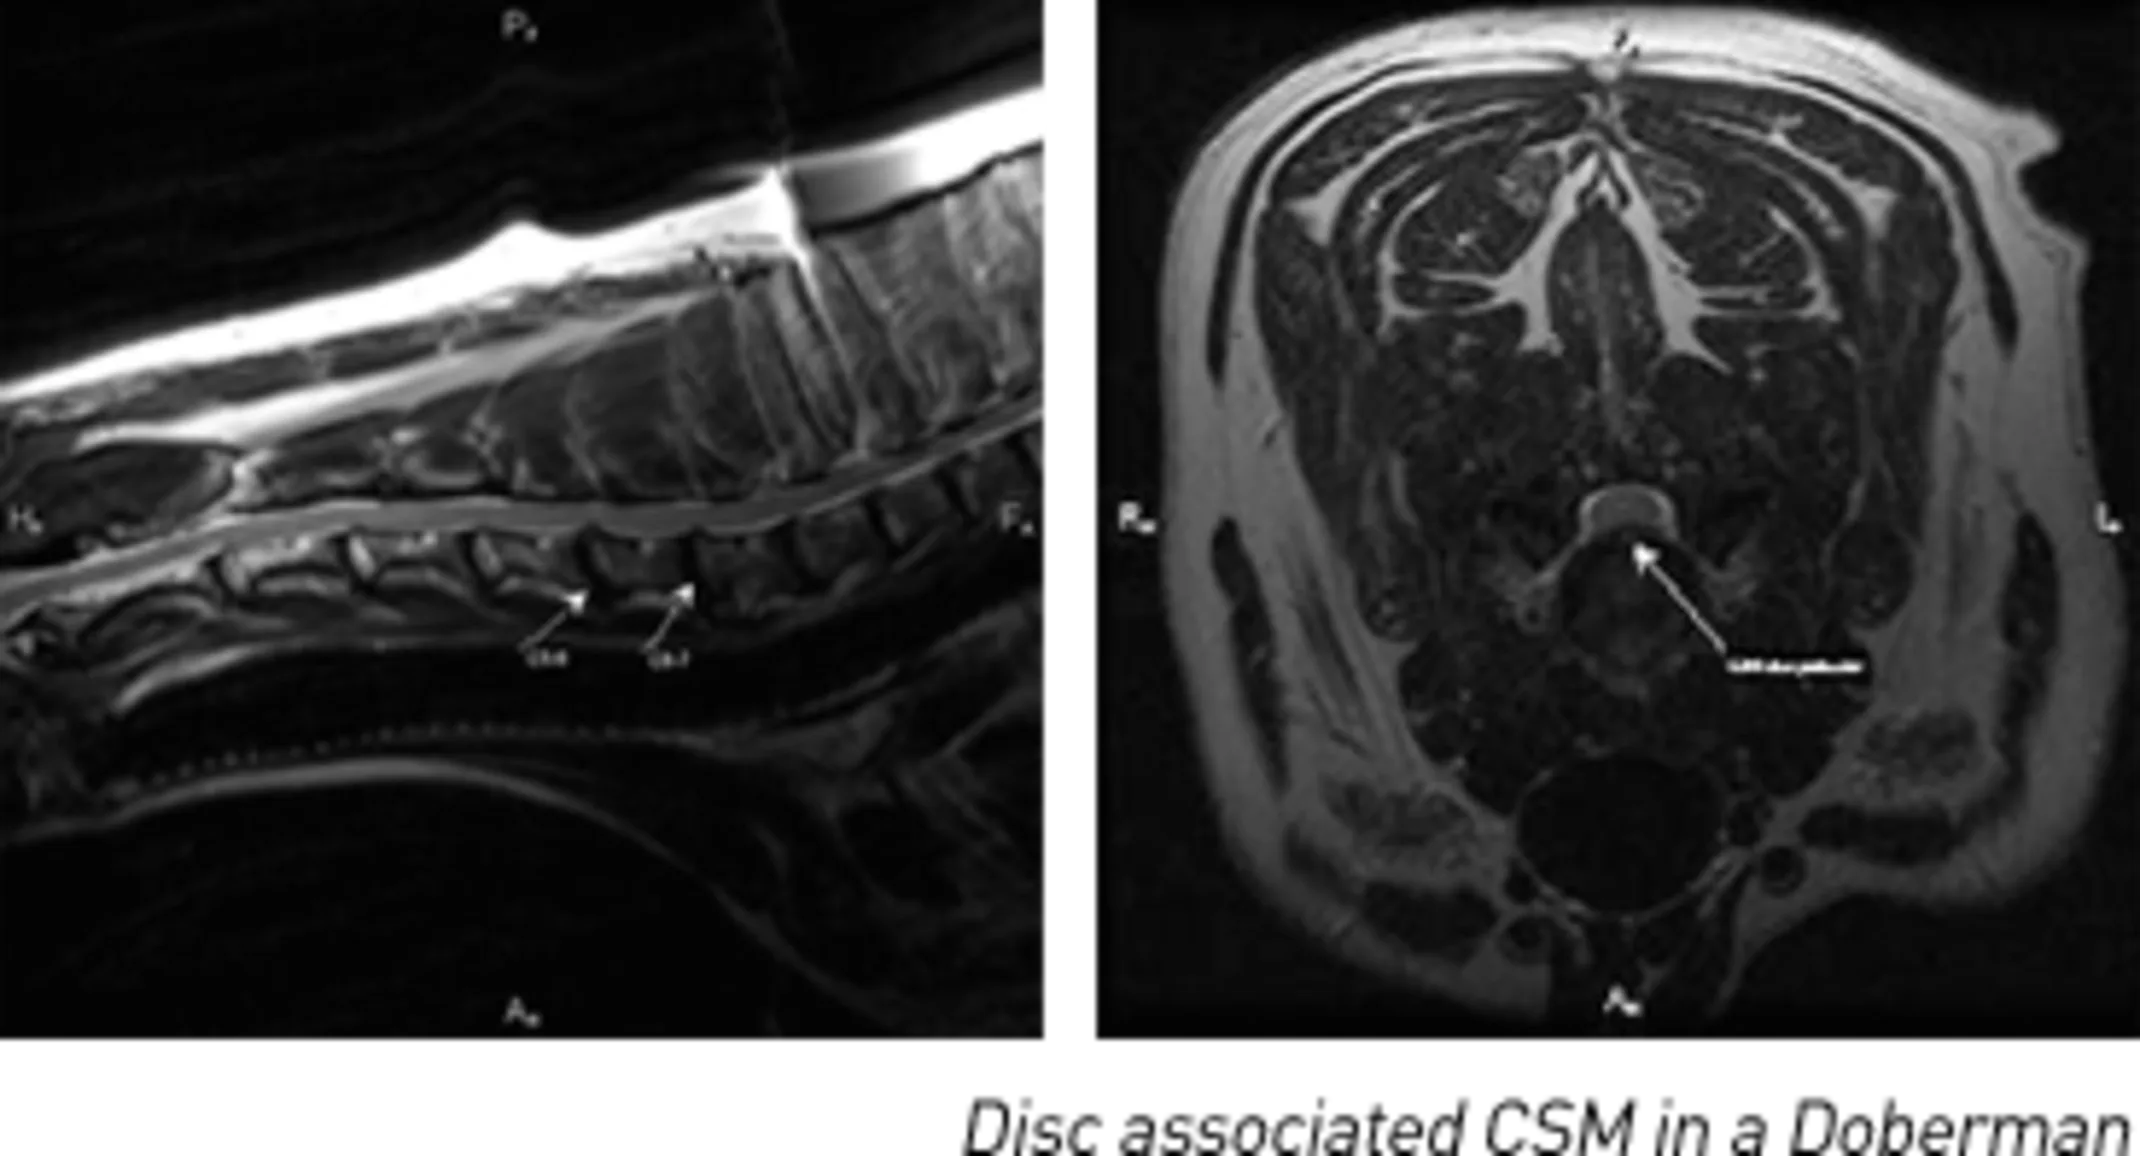

Disc-associated CSM is seen in middle aged to older large breed dogs; Doberman Pinschers are most often affected followed by Rottweilers and Bernese Mountain Dogs. Spinal cord compression most commonly occurs at C5-6 and C6-7 due to Type II disc degeneration and protrusion (leading to ventral compression); thickening of the vertebral ligaments and vertebral body instability may also contribute to cord compression.

Imaging of the cervical spinal cord with an MRI examination or a CT/myelogram study demonstrates the location and extent of cervical spinal cord compression. Lesions can also be classified as dynamic (compressions that worsen or improve with different neck positions) or static.